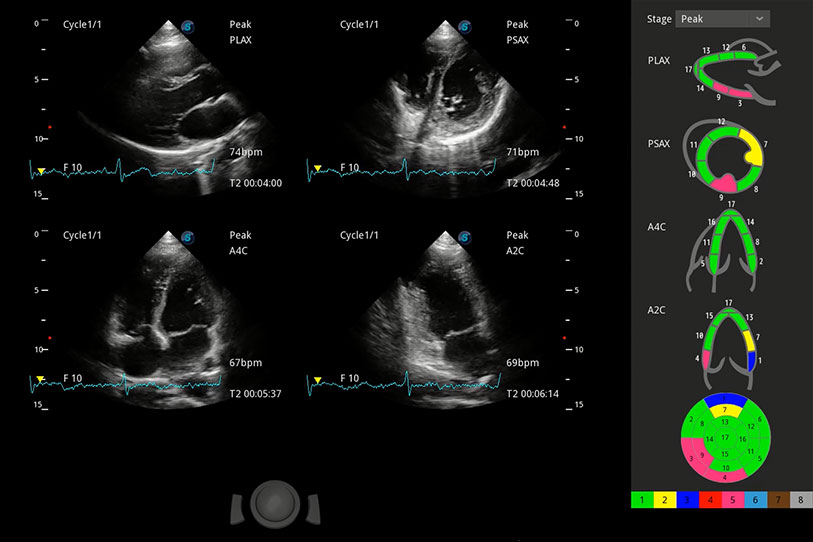

能夠基于左心室壁追蹤和辛普森法,自動(dòng)計(jì)算射血分?jǐn)?shù),支持多個(gè)可移動(dòng)點(diǎn)描跡,與手動(dòng)測(cè)量相比,極大節(jié)省了動(dòng)物醫(yī)生的時(shí)間和精力。

具備多種協(xié)議可選,同時(shí)支持17階段劃分法和專業(yè)的SE報(bào)告。